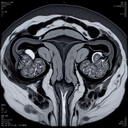

МРТ гістеросальпінгографія прохідності маточних труб

МРТ гістеросальпінгографія – це сучасний метод діагностики, який використовується для оцінки прохідності маткових труб. На відміну від традиційної рентгенівської гістеросальпінгографії, МРТ не використовує іонізуюче випромінювання, що робить її менш навантажувальною для організму. ### Процедура: 1...